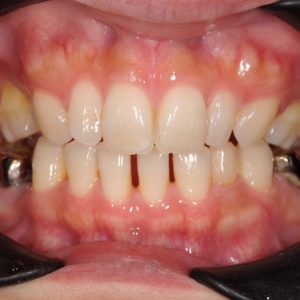

虫歯の治療、矯正の相談をご希望され来院されました。お口の中を診査(レントゲン写真、口腔内写真、視診)させていただいたところ、虫歯については問題なくきれいに歯磨きされているようでした。 正面から見るとジグザグしており、お口 […]

全体的な歯並びの矯正治療を行いました。治療期間は3年間。

ジグザグの歯並びを気にされてご来院されました。. 見た目の問題も大切ですが、それ以上に清掃がしにくいために虫歯・歯周病に非常になりやすく、不正咬合(良くないかみ合わせ)は顎の関節に負担をかけてしまい顎関節症を引き起こす可 […]

歯の大きさに対する顎の大きさのスペース不足により歯が並びきらず、ジグザグの歯並びおよび上の前歯が出っ歯になっていました。 左右4番の歯を抜歯することにより歯を並べるスペースを確保し、歯並びを揃えました。 全体の歯並びが綺 […]